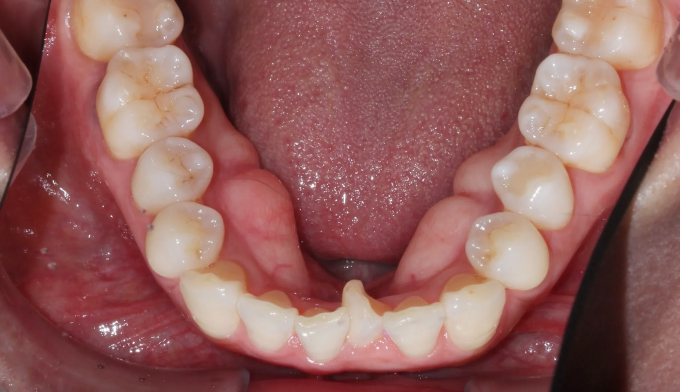

40대가 넘어가면서부터 앞니들이 점점 가운데로 몰리고 삐뚤빼뚤해지는 경우가 많습니다.

우리의 이들은 어릴적 맹출한 위치에 평생 있지 않고, 긴 시간에 걸쳐서 앞쪽으로 쏠리기 때문입니다.

삐뚤빼뚤한 정도가 심하지 않다면 간단한 앞니 부분교정만으로 충분히 배열이 가능하지만, 확보해야할 공간이 크다면 전체교정을 통해 어금니를 뒤로 보내야 앞니를 배열할 수 있는 공간을 만들 수 있습니다.

총 치료기간은 14개월 소요되었습니다.